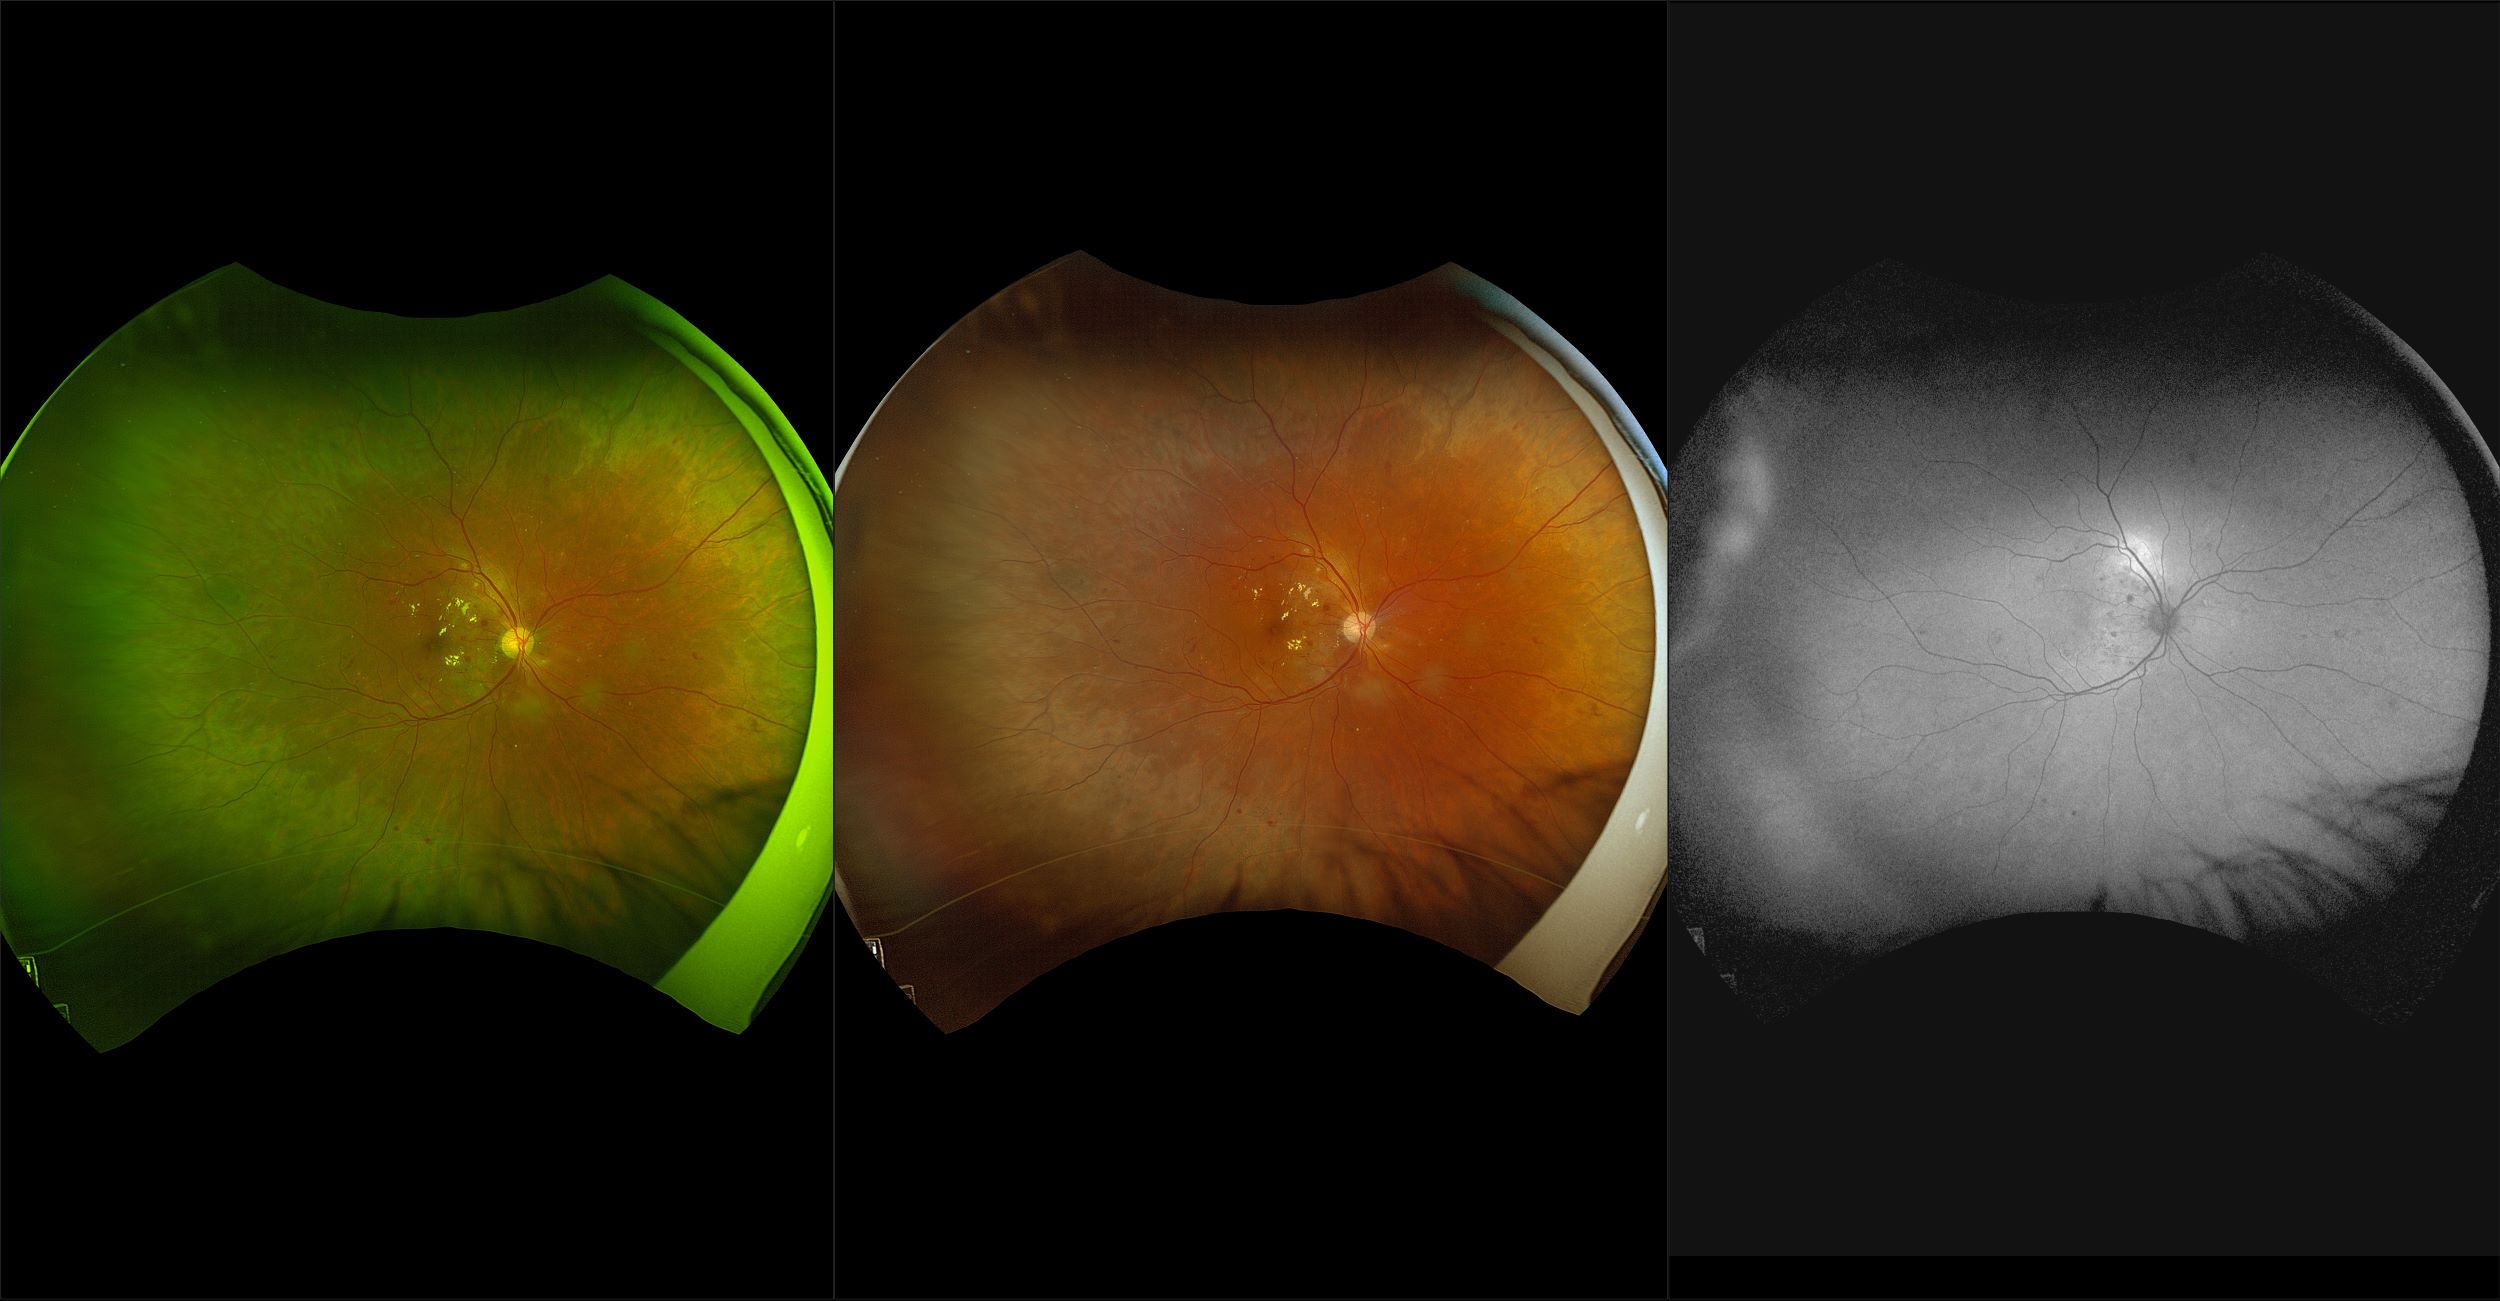

California - AMD, RG, AF

Age-related macular degeneration is found in two forms 1. Dry early form. 2. Wet (serous leakage or whole blood). Early dry form typically has drusen (usually around 63u) and RPE degeneration and only needs periodic follow-ups, intermediate dry form has large drusen (>125u) and RPE degeneration and proliferation which requires examinations every 3 to 6 months depending on the severity of the presentation.